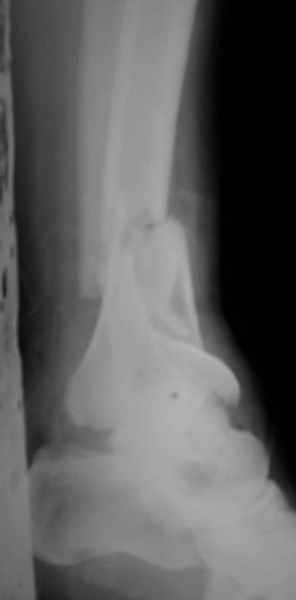

Открытый оскольчатый перелом н/3 голени.

Здравствуйте, коллеги! 16/10/06 г. В отделение поступила больная с производственной травмой - Открытый оскольчатый перелом метафиза и метадиафиза обеих костей правой голени со смещением отлоков.

При поступлении произведено ПХО ран, наложена система скелетного вытяжения за пяточную кость. Проводилась антибактериальная терапия, перевязки. На данный момент раны зажили первичным натяжением, швы сняты. Сохраняется лёгкая гиперемия в области одной из ран. Планируя оперативное лечение хотелось бы узнать Ваше мнение о наиболее рациональном методе лечения данного перелома.

Здравствуйте коллеги! В данной ситуации я полностью согласен с мнением Александра Николаевича! Практически любой внутрисуставной(тем более приведенный на снимках) перелом требует открытой репозиции.Судя по приведенным рентгенограммам, в области дистального тибио-фибулярного сочленения имеется "минус" ткань на tibia, которая может потребовать костной пластики.Метод фиксации любой,главное ранние движения в суставе. С уважением Руслан Ш.

К слову, тема этого обсуждения обозначена неточно, тут перелом дистального суставного конца типа 43-C, а не "открытый оскольчатый перелом н/3 голени", т.е. диафизарный, 42-.

Действительно, речь идет о сложном внутрисуставном, да еще и открытом переломе 43С.3.